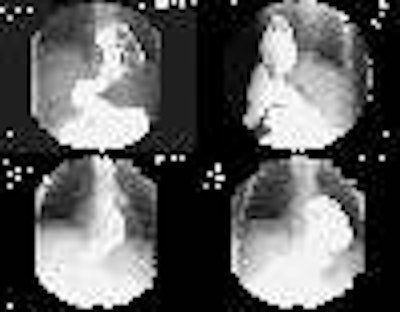

Morgagni Hernia:

The infant in the images below was referred for the evaluation of a "cystic anterior mediastinal mass." The "mass" was confirmed to be large bowel loops on a barium enema exam.

BE: